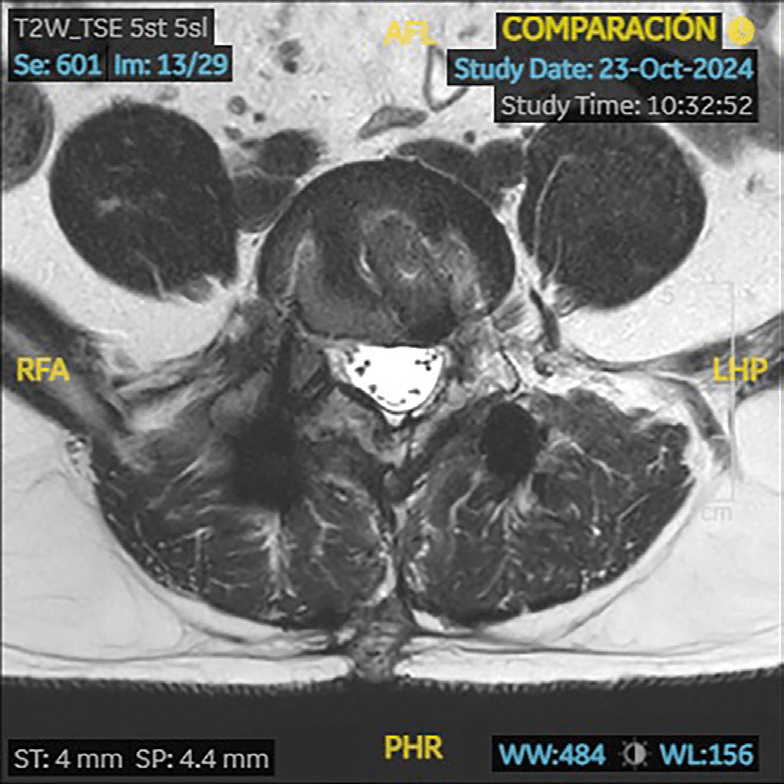

RM (09/2023): cambios postquirúrgicos en L4/L5 con signos de sobrecarga mecánica en platillos vertebrales. Estenosis severa de forámenes neurales L4/L5 por hipertrofia de facetas articulares y por patología discal. Patología en el nivel adyacente L3/L4 con discopatía sin hernia y artropatía degenerativa que producen estenosis moderada foraminal bilateral.

En localización extraforaminal derecha L4/L5, engrosamiento focal sólido de la raíz L4 que mide 15 mm de diámetro y que se realza de forma homogénea tras la administración de contraste intravenoso; sugestivo de tumoración de estirpe neural, neurinoma o neurofibroma.